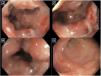

Colonoscopy. (A) Ulcers and pseudopolyps in the mucosa are observed, along with abundant mucus. (B) The reduced lumen is passable and there is inflammation and edema of the mucosa. (C) Signs of bleeding and fibrinopurulent material can be observed. (D) Multiple ulcers smaller than 5 mm, with well-defined 3-5 mm edges, are shown.